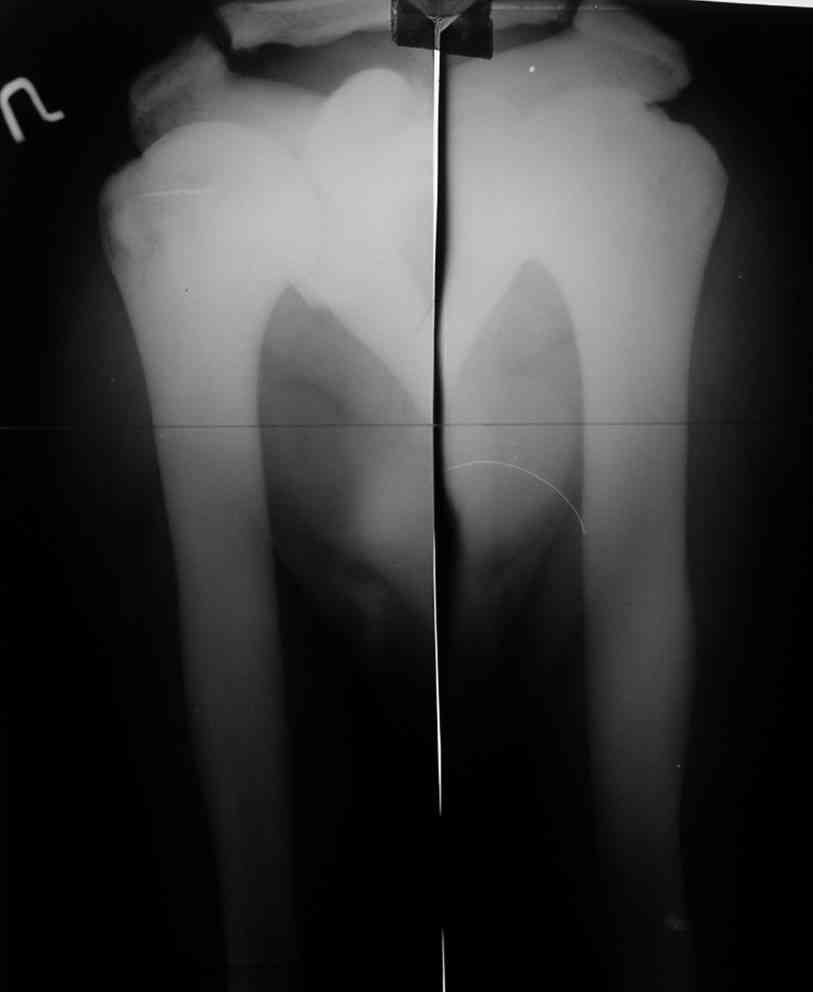

Уважаемый Константин Иванович! Полностью согласен с проф. Михайловым, данный случай не похож на мраморную болезнь, при которой имеется резкое, строго симметричное и генерализованное уплотнение костной ткани (остеопетроз), и кость оказывается построенной преимущественно из гомогенного компактного костного вещества. Для примера привожу случай из архива нашего института (бедренные, плечевые кости и таз, рис 1,2,3)

Изменения структуры костей у Вашего пациента больше похожи на полиоссальную форму фиброзной дисплазии или болезнь Педжета, возможены также инфаркты костного мозга б.берцовых костей. К сожалению, качество снимка не очень хорошее, непонятно, сохранен ли кортикальный слой б.берцовых костей по передней поверхности.

Представленные Вами данные о пациенте 57 дет с болезнью Альбертс-Шенберга чрезвычайно интересны, но диагноз вызывает большие сомнения. Для мраморной болезни характерно прееобладание склероза, а на представленных рентгенограммах преобладает симметричная дезорганизация архитектоники губчатой кости в эпиметафизарной зоне дистальных отделов бедер и голеней.

Остеопетроз характеризуется болями в костях, а на ренгене следы множественных несращении длинных трубчатых костей и “белая-мелоподобная” кость.